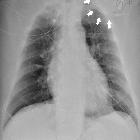

Plain radiograph

It can be suggested when the leads on a previously well-positioned device retract and begin to wrap around the subcutaneous portion of the device.